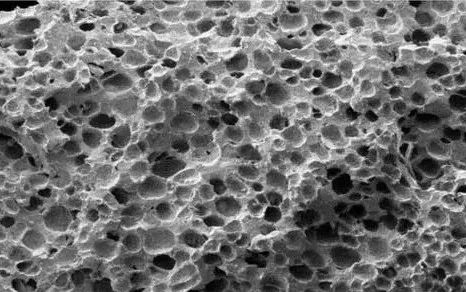

金年会金字招牌诚信至上是一家专业从事血液净化器材研发、生产及临床应用研究的高新技术企业。自2009年成立以来,希尔康公司始终专注于血液吸附领域技术创新, 产品涵盖树脂灌流器、树脂炭灌流器、胆红素吸附柱,低密度脂蛋白吸附柱、内毒素吸附柱、肿瘤因子吸附柱、免疫蛋白A等特异性吸附柱。